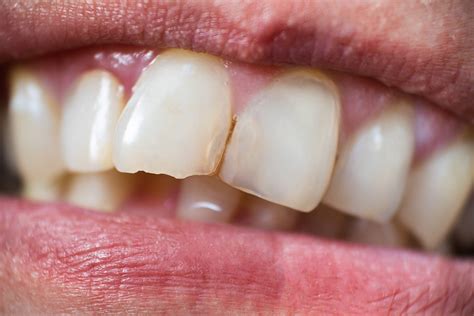

The severity and type of chip can vary, ranging from minor cosmetic issues to more significant structural damage. The most common types of chips include:

- Craze lines: These are tiny cracks or lines that occur on the enamel, the outer layer of the tooth. Craze lines are often superficial and don’t cause any pain or significant damage. They are mainly an aesthetic concern.

- Minor chips: These chips typically affect the tooth’s enamel or the dentin, the layer underneath. They may appear as small fractures or missing parts of the tooth. While not usually painful, they can cause sensitivity or discomfort.